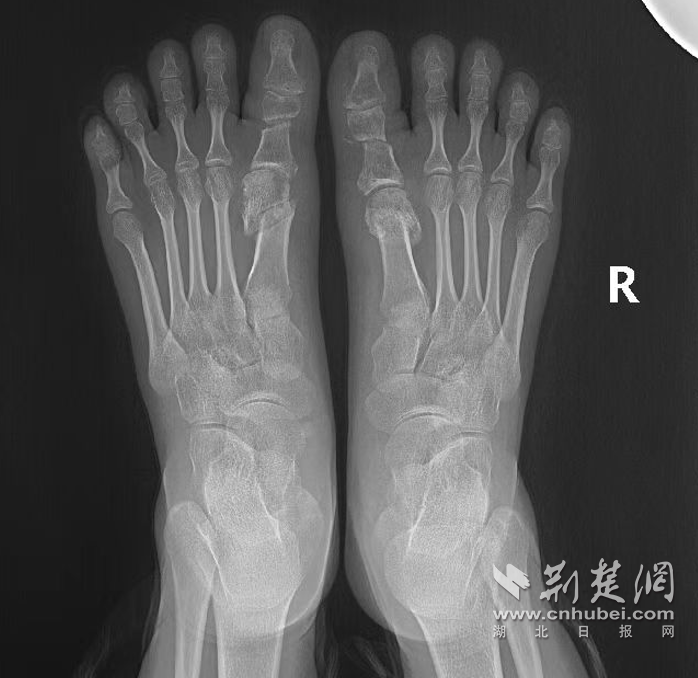

荆楚网(湖北日报网)讯(通讯员 张莉莹 魏晓燕)18岁的患者茜茜(化名)因遗传性重度拇外翻畸形,长期无法正常穿鞋子,严重影响外观与日常行走。在襄阳市中医医院足踝骨科就诊后,经科主任王春玲系统评估,诊断为双足拇外翻,符合手术指征,为其开启日间手术模式,实行局麻下双足拇外翻截骨矫形整复术,即局麻下拇内收肌松解+骨赘削除+第1跖骨截骨术。

术后6小时茜茜生活自理,独立完成如厕、洗漱、饮水等;术后24小时复查X线示截骨对位良好。在确保手术部位安全的前提下,王春玲指导其扶拐出院,并制定个性化康复计划,使其患肢通过科学、渐进的负重刺激,促进愈合,恢复功能,预防并发症。术后3个月随访,茜茜双足拇指功能接近正常,畸形矫正满意。

手术后。 通讯员 供图